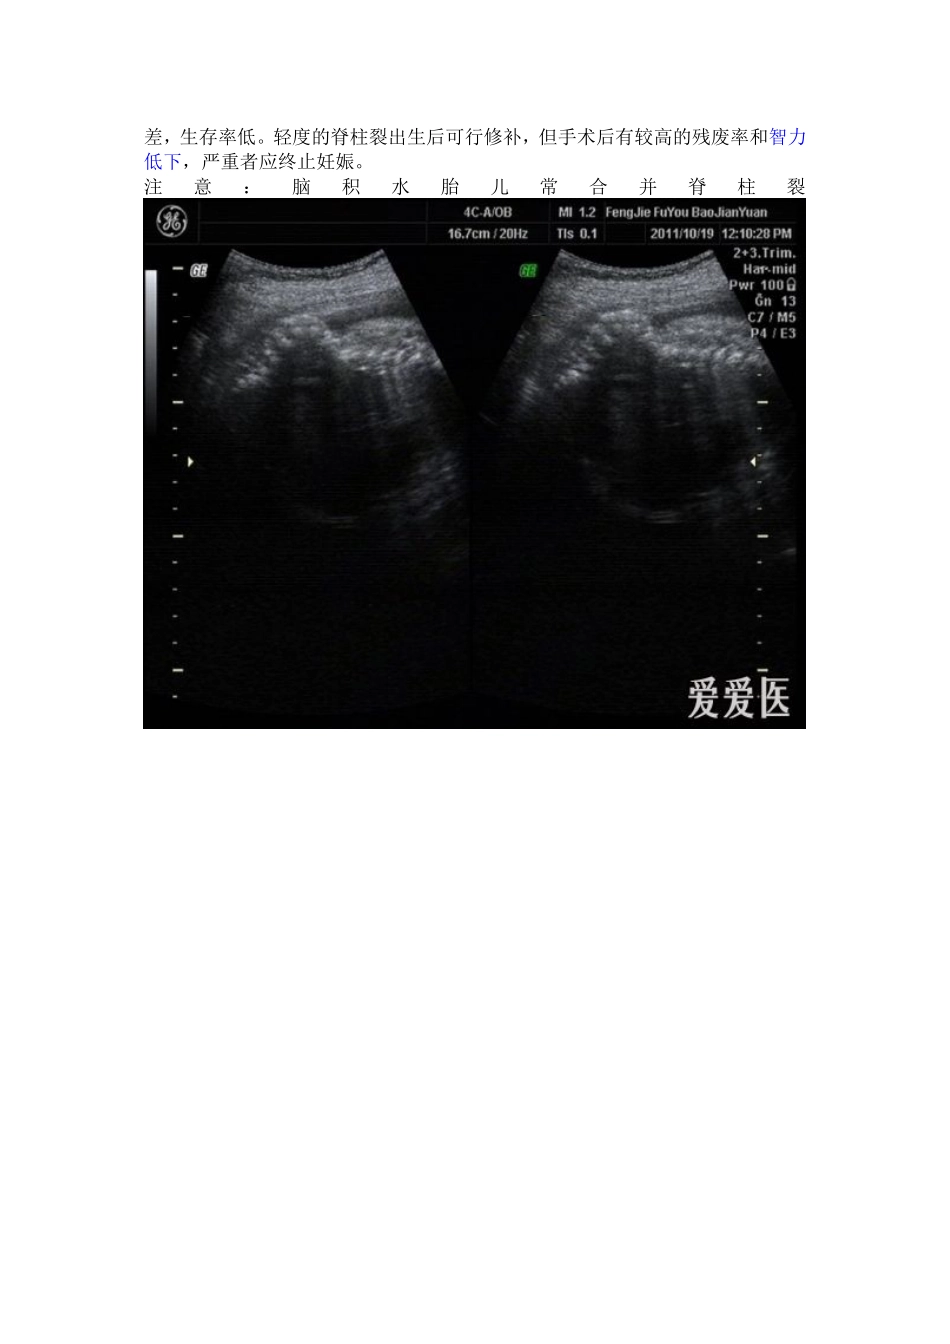

脑积水:是由于各种原因引起脑脊液在脑室腔内过多积聚,出现脑室扩张。脑积水可使胎头体积增大,颅缝增宽,骨质变薄。脑室扩张或腩积水最常见的原因是中脑导水管狭窄,其他常见原因包括:颅内感染导致脑脊液产生、吸收和回流障碍;脑结构发育异常;神经管畸形;染色体异常;多发畸形综合征。因此当发现颅内异常积液时,一定要仔细扫查其他可能的病变。超声表现:1.脑室扩张诊断标准妊娠20周后,侧脑室或小脑延髓池宽度超过10mm就应警惕腩室扩张积液,应密切随访观察其转归。若追踪观察过程扩张进行性增大,可诊断脑积水。正常胎儿在妊娠20周后,侧脑室外恻至中线距离与脑中线至颅骨板之间的距离之比(腩室率)小于l/3,若大干1/3即提示脑积水的存在。2.中脑导水管狭窄表现双侧侧脑室和第三脑室扩张,进行性加重。严重时侧脑室极度扩张,脉络膜从漂浮往脑室中,大脑组织受压变薄、脑中线漂浮,头围增大,脑室率多大于l/2,常合并羊水过多,第三脑室也相应扩张,见图5―2―22。交通性脑积水也有上述表现,偶尔可以见到蛛网膜下腔扩张、第四脑室扩张。鉴别诊断:脑积水应与脑实质内病变引起的局限性积液鉴别。由于颅内感染、颅内血管闭塞、脑组织发育不良等因素导致脑积液改变,表现为颅内出现不对称局限性液性暗区、相应的颅内结构缺失或受压变形,例如水脑、孔洞脑(脑穿通畸形)等。注意:严重的脑积水诊断并不难,但20周以前,个别的单纯侧脑室扩大,可能为暂时性的失调,需定期监测,谨慎诊断。二.胎儿脊柱在骨化过程中若不融合,或仅部分融合,则形成脊柱裂(spinabifida),常合并脊膜膨出、无脑等其他中枢神经系统畸形。绝大多数脊柱裂为背侧裂,发生在腰椎或骶椎。其发生与染色体异常、环境因素有关。大部分脊柱裂为开放性,小部分为隐性脊柱裂,后者无脊膜膨出、皮肤和皮下软组织正常,超声容易漏诊。超声表现:1.椎骨变形、缺损从胎儿脊柱的背面冠状扫查,脊柱背侧椎弓的两条平行串珠状强回声间距离局部变宽,横切而上在椎管外围由椎体和椎弓组成的闭合性三角形变成开放性,两椎弓分开,呈V形或U型。可以合并脊柱侧弯或后突畸形。2.脊膜膨出开放性脊柱裂在脊柱病变的部位,皮肤、皮下软组织也有缺损,皮肤延续性中断,局部见大小不等、边界清晰、有薄壁的囊性膨出物,常随胎动在羊水中漂动,局部可见脊椎裂声像。轻度脊膜膨出尤其是位于骶尾部时,容易漏诊。3.合并异常常合并颅内积液。由于脊膜膨出、枕骨大孔疝形成,造成颅内负压,小脑受挤压变形,反折呈“香蕉形小脑”,两侧顶骨内陷形成“柠檬头”征。另外常合并马蹄内翻足、羊水过多等。鉴别诊断:脊椎裂脊膜膨出应与骶尾部畸胎瘤鉴别。后者囊肿内为不均质混合回声、表面有皮肤覆盖、脊椎骨无异常,藉此声像可以鉴别。临床评价:脊柱裂预后差,生存率低。轻度的脊柱裂出生后可行修补,但手术后有较高的残废率和智力低下,严重者应终止妊娠。注意:脑积水胎儿常合并脊柱裂